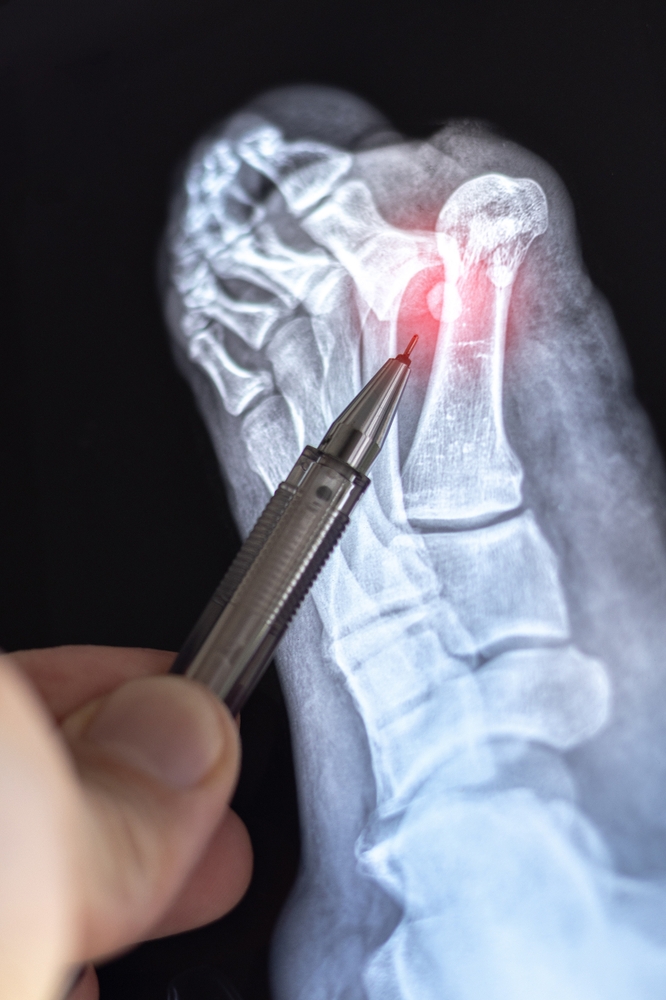

Nustatant Lisfranco sužalojimą, atliekamas fizinis pėdos ištyrimas, atsižvelgiama į jos išvaizdą, jautrumą ir stabilumą. Taip pat svarbu tiksliai apibūdinti, kaip susižalojote ar kada pirmąkart pajutote simptomus.

Norint patikslinti diagnozę, gali būti atliekami instrumentiniai tyrimai:

- Pėdos rentgeno nuotrauka;

- Magnetinio rezonanso tomografija (MRT);

- Kompiuterinė tomografija (KT).

Šie tyrimai leidžia įvertinti, ar pažeisti kaulai, raiščiai, ar abu.